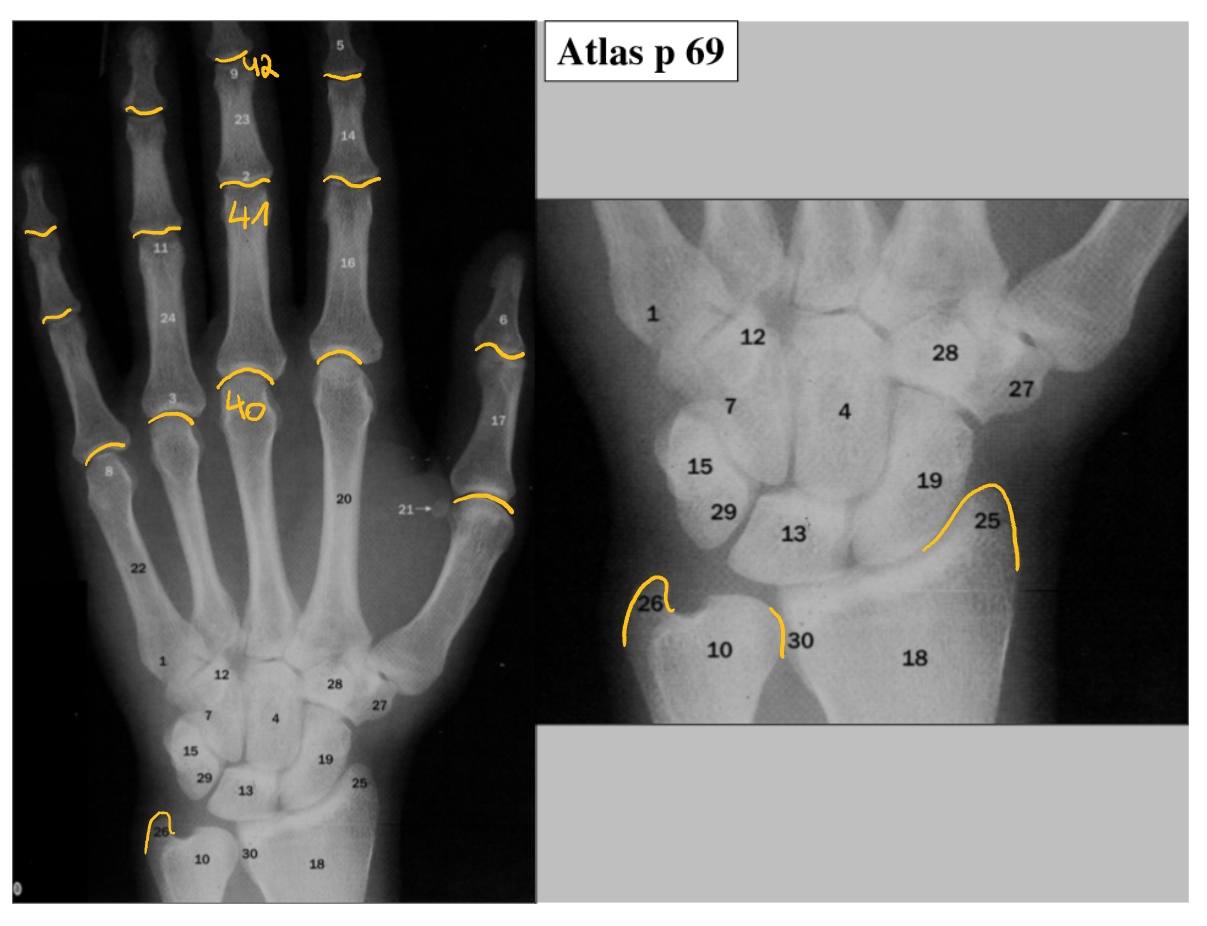

basis metacarpaal 5

os scaphoideum

os lunatum

os triquetrum

os pisiforme

os hamatum

os capitatum

os trapezoideum

os trapezium

processus styloideus radialis

processus styloideus ulnaris

distale radio-ulnaire gewricht

MCP: metacarpo-falangeale gewrichten

PIP: proximale-interfalangeale gewrichten

DIP: distale-interfalangeale gewrichten

flexor retinaculum

n. medianus

zit in de carpale tunnel

flexorpezen